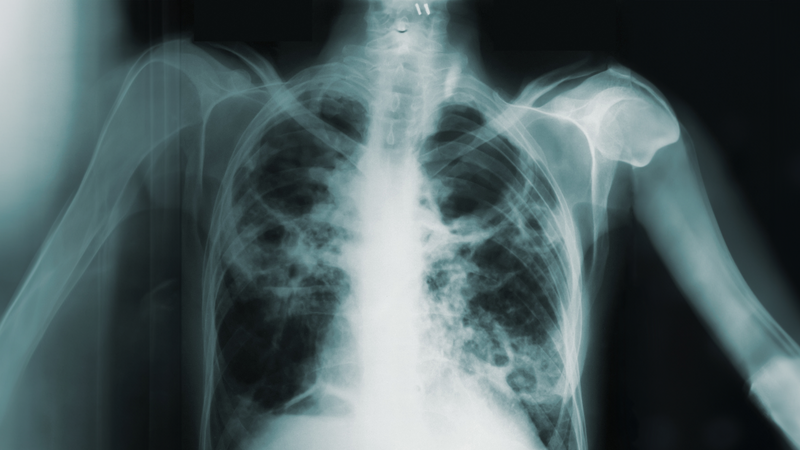

Non-tuberculosis mycobacteria (NTM) represent an increasingly significant cause of pulmonary and extrapulmonary infections, sometimes misinterpreted as tuberculosis (TB) owing to overlapping clinical and microbiological characteristics. Conventional diagnostic approaches such as Ziehl-Neelsen staining and culture in Mycobacterial Growth Indicator Tube (MGIT) system, are constrained by extended incubation times and are still insufficient for accurate species differentiation and are limited by prolonged incubation periods. Recent molecular and genomic advance have transformed NTM diagnostics by enabling rapid, specific and high-resolution identification. Line probe assay (e.g, Genotype Mycobacterium CM/AS) and multiplex PCR have enhanced the ability to distinguish between NTM species such as Mycobacterium absessus, M. fortuitum, and M. avium complex and M. tuberculosis complex which is essential for proper treatment and epidemiological mapping. Among newer proteomic platform, Matrix-Assisted Laser Desorption/Ionization – Time-Of-Flight (MALDI-TOF) mass spectrometry has emerged as a transformative, cost-effective technology capable of identifying Mycobacterium species directly from culture isolates through protein fingerprinting. It provides rapid, reproducible, and highly discriminatory identification between closely related species. Next-generation sequencing (NGS) and whole genome sequencing (WGS) approaches now offer unprecedented insight into species identification, strain typing, and drug-resistance prediction, complementing traditional culture-based susceptibility testing. Newer techniques such as metagenomics NGS (mNGS), targeted NGS (tNGS) multilocus sequence typing (MLST), and Mycobacterial Interspersed Repetitive Unit-Variable Number of Tandem Repeats (MIRU-VNTR) genotyping facilitate subspecies-level resolution and real time outbreak surveillance. Moreover, molecular beacons, insertion sequence (IS) analysis, and repetitive sequence-based polymerase chain reaction (Rep-PCR) enhance detection sensitivity even in paucibacillary samples. The integration of genomic data with automated diagnostic system promises earlier intervention, accurate species delineation, and improved patient outcome.